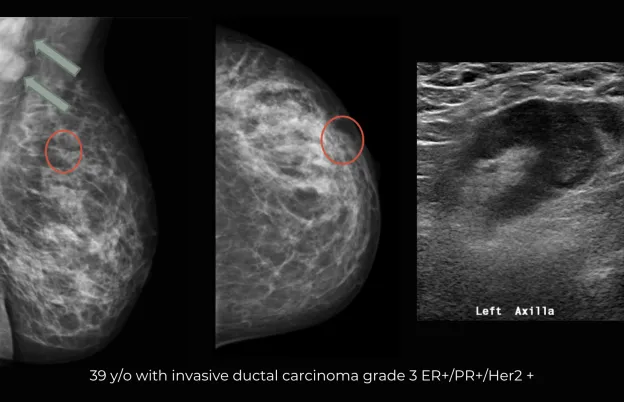

Correlate mammography and ultrasound examinations to identify suspicious areas in both imaging methods

Review case studies for correlation